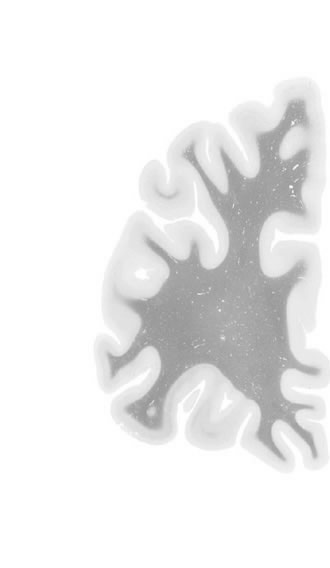

Frontal sections (Nissl) from the Atlas Brain:

Macroscopy

Microscopy

Slice ID:

r1-0251

Plate NR:

04-05

Position:

-40,5 mm